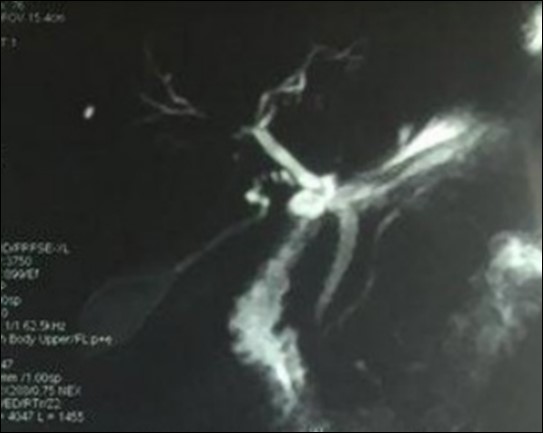

We report the case of an asymptomatic 49 years old male patient, in which a routine check objectified a biological cholestasis (gammagmutamytransferase = 2-3N and ALP = 5-6 N without hyperbilirubinemia or cytolysis). Nos past medical facts were noted. Abdominal ultrasound, viral markers and antibodies measurement (Ac Anti-nuclear, anti-Mitochondrial, anti-LKM1, Anti-cytoplasmic) were normal. Magnetic resonance choalngiopancreatography objectified multiple biliary strictures and parietal irregularities evocative of SC (Figure 1). Colonoscopy showed no associated inflammatory bowel disease. Patient received high doses of ursodeoxycholic acid (20mg/kg) for the SC with partial improvement of liver function but persistence of a marked rise in ALP level. In order to better characterize the nature of ALP, a dosage of ALP isoenzymes was performed and objectified a predominant bone fraction (83%), while liver fractions H1 and H2 were respectively of 12% and 4%. X rays objectified bone condensations with a fibrillar appearance and bone hypertrophy suggestive of PD (Figure 2). A bone scan made for lesions mapping showed a multifocal PD (Figure 3). The patient was treated by bisphosphonates (injections of zoledronic acid), which was associated with a decreasing in ALP level after 6 months.

Figure 1.Magnetic resonance cholangiopancreatography showing multiple biliary strictures and parietal irregularities